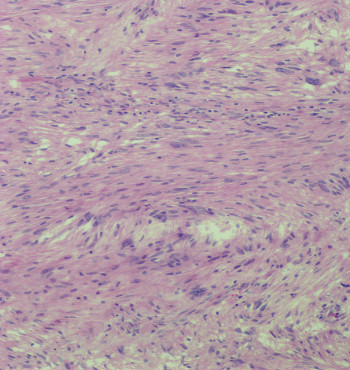

Cortesía de la Dra. Claudia Haydée Caro Sánchez, del INCAN.

Mujer de 57 años, con dolor abdominal leve de predominio postprandial. En la tomografía computada se evidenció una lesión en curvatura menor de 5 cm, dependiente de la pared. No se realizó biopsia y se programó para resección de lesión en cuña.

2.- ¿Qué estudios especiales solicitarías para apoyar tu diagnóstico?

a) PS-100 y SOX-10

b) Vimentina, AAML

c) CD117, DOG-1, CD34

d) AAML, h-Caldesmona